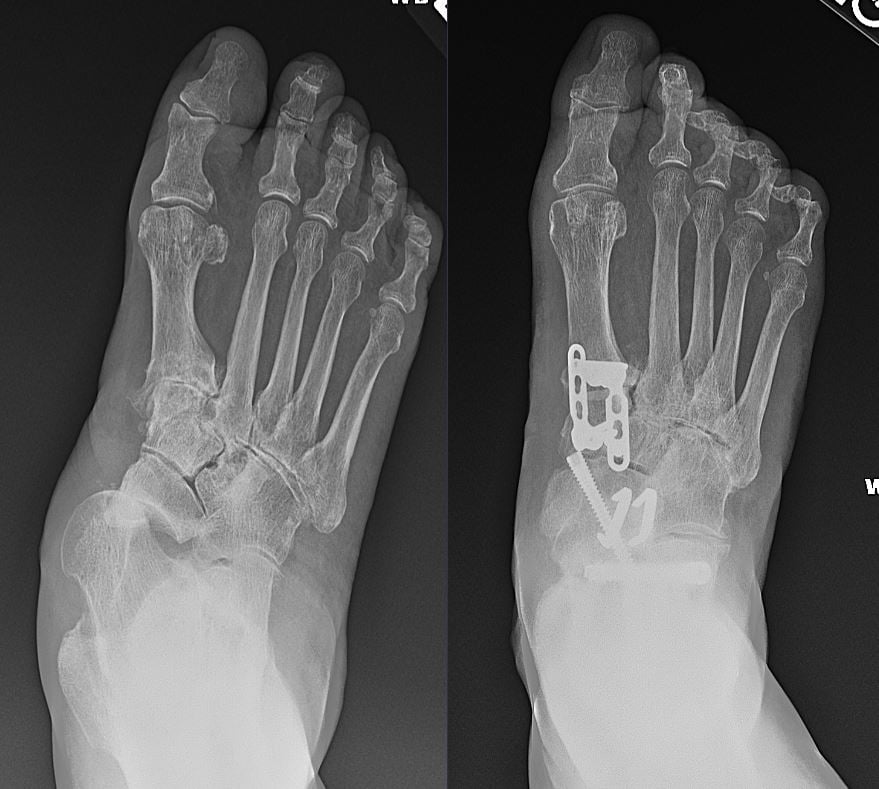

Patient image of: Bill Morton

I had a badly deformed arthritic right foot and had reached a point where it was very painful and difficult to walk. Prior to seeing Dr. Cody, I had met with a leading university hospital foot surgeon. He told me the surgery on my foot would take seven hours and he couldn’t guarantee that I’d see any improvement after surgery. Several months later and after further deterioration of my ability to walk, I met with Dr. Cody. After taking x-rays of my foot she said she could repair my foot and proceeded to describe the surgery. Immediately post-surgery after the nerve block wore off, I had less pain than I did pre-surgery. One year later, I’m walking without any pain and doing all of my normal life activities. Needless to say, I’m extremely satisfied with the surgical outcome. I highly recommend Dr. Cody and have already referred 2 friends to her.